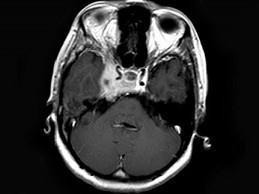

问题 女,34岁。右侧听力下降,耳鸣2个月。MRI平扫及增强扫描如图示,最可能的诊断是 ( )

选项 A、动脉瘤 B、未见异常 C、脑膜瘤 D、神经源性肿瘤 E、鼻咽癌

答案 E